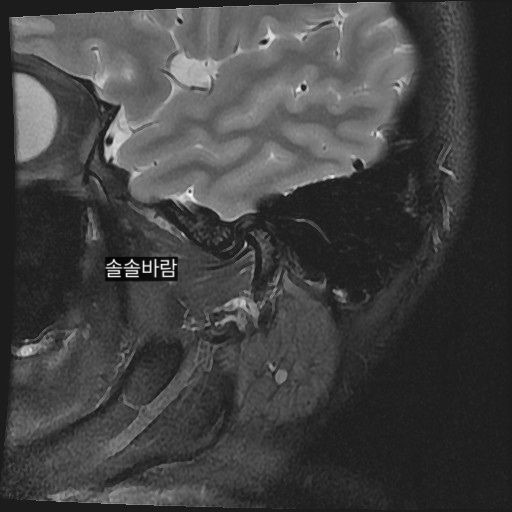

구강내과 턱 MRI 어느 사진이 우측? 좌측?인지 어떻게 보나요? 디스크 두꺼워짐 심한가요?ㅜ

구강내과 턱 MRI 사진 보는데 귀 위치가 다 똑같아서요

어느 사진이 우측? 좌측?인지 어떻게 보나요?

그리고 사진 상 디스크 두꺼워짐 심한가요?ㅜ

현재 사진만으로는 정확히 왼쪽이나 오른쪽이다 라고 할 수 없습니다. 이는 데이터 상의 reference가 필요하며 보통은 해당 부위가 질문자님 기준으로 좌측일 가능성이 가장 크나 이는 좌우 반전을 할 수 있기 때문에 무조건 좌측이라고 할 수 없습니다. 현재 개구시와 폐구시에 보았을 때 condyle (아래턱 부위의 일부)가 disc를 넘어가지 못하고 있으며 이러한 경우 개구제한이 있거나 넘어가더라도 소리가 나면서 넘어갈 수 있습니다. 일부 염증도 보이고 있으므로 내과적인 치료를 하셔야 할 것으로 보입니다.